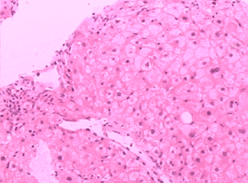

3、組織學特徵:黏膜下靜脈擴張,無或僅有輕微炎性細胞浸潤為其特徵性表現。其他還有黏膜下小動靜脈壁增厚,靜脈動脈化。黏膜橫斷面毛細血管面積較正常增大。胃黏膜毛細血管發育不良,散在裸露於胃腔內,表面無上皮組織覆蓋。胃黏膜小動脈變直,螺鏇度減輕。小血管注射研究發現,黏膜下動靜脈分流廣泛開放,電鏡觀察顯示毛細血管顯著擴張,內皮小孔擴大,血管內皮與基底膜連線不緊密,出現間隔,血管基底膜不連續,毛細血管基膜與上皮細胞基膜之間距離變寬,上皮細胞腫脹變性。紅細胞從破損的上皮處外滲,並出現於上皮間隙之間。因內鏡活檢取材小且表淺,僅有50%的活檢標本病理見有毛細血管擴張。